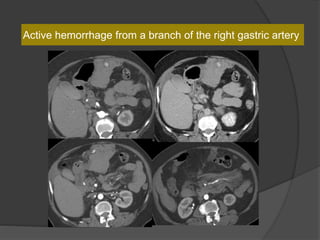

Case 8: 64 F with chest pain, abdominal back pain,

evaluate pulmonary embolism or dissection, CT A/P

normal. 24 hrs later right flank pain and hypotension ,

?aortic dissection

19 HU

40 HU

60 HU

Active hemorrhage from a branch of the right gastric artery

Dx:Mesenteric vasculitis with active hemorrhage

Take home points-

1. Sentinel clot sign

2. Recognize the appearance of

extraluminal contrast indicative of

active hemorrhage.

3. Vessel morphology to detect the

cause for bleed